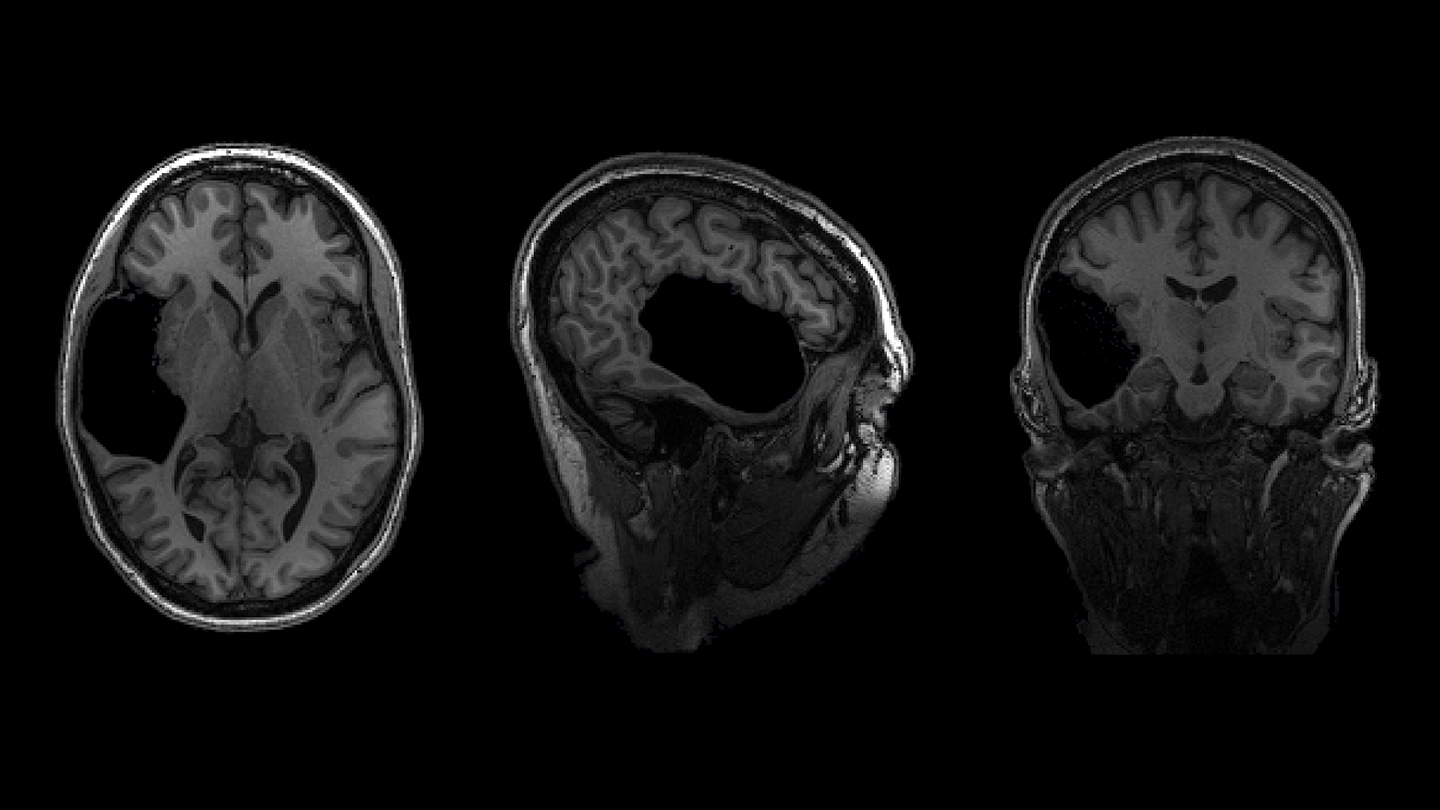

Elyse G.’s brain is fabulous. It’s also missing a big chunk

Nick Dee, the neuroscientist charged with quickly cutting the chunk into neat pieces, confers with his colleagues. “We can trim off that ugliness on the side,” he says. The “ugliness” is the brain’s connective tissue called white matter. After Dee and his team do their part, pieces of the woman’s brain will be whisked into the hands of eager scientists, where the cells will be photographed, zapped with electricity, relieved of their genetic material and even infected with viruses that make them glow green and red.